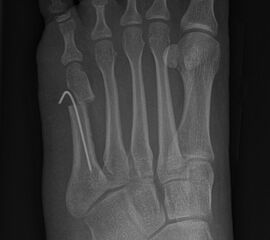

Knick-Senk-Platt-Fuß Korrektur mit dem Canalis Tarsi Spacer

In der Korrektur des schmerzhaften, aber flexiblen Knick-Senk-Fußes oder Plattfußes ist die Schraubenarthrorise mit einem Sinus tarsi oder besser bezeichnet als Canalis tarsi Spacer und alternativ mit einer Calcaneus-Stopp-Schraube seit vielen Jahren ein etabliertes Verfahren und führt zu einer kompletten Korrektur von flexiblen Knick- und Plattfuß-Fehlstellungen (Abb. 7). Die nötige Schnittlänge über dem Sinus tarsi beträgt für beide Verfahren 1 cm.

Abb. 7 a-e: Knick-Senk-Fuß prä- und postoperative Situation (a-b), ventrale und dorsale Ansicht (c-d). Laterale Ansicht des Hautschnittes über dem Sinus tarsi (e).